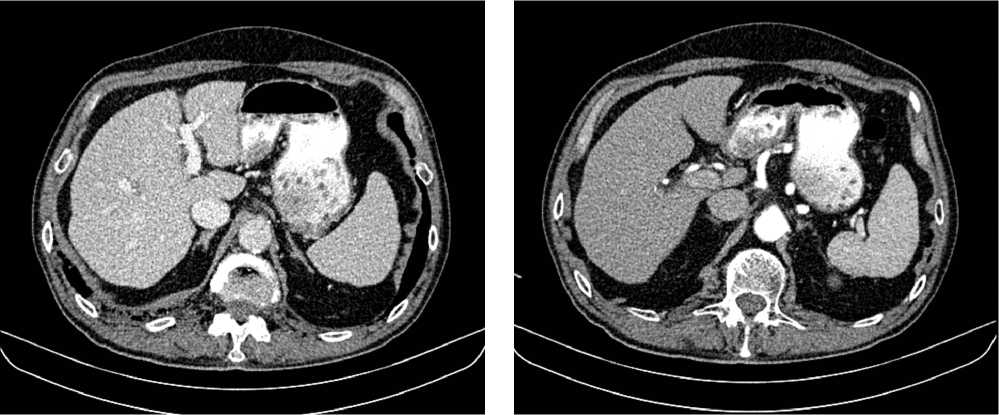

По решению онкологического консилиума пациенту начат ПХТ 1 линии в режиме FOLFOX + бевацизумаб. С 02.09.2022 проведено 3 цикла ПХТ 1 линии, по результатам контрольных обследований зарегистрировано прогрессирование процесса за счет роста образований печени до 64 × 46 мм и появления линзовидного образования между передней поверхностью прямой кишки и задней поверхностью предстательной железы размерами 47 × 15 × 25 мм (рис. 7, 8).

Рис. 7. Результаты компьютерной томографии органов брюшной полости у пациента 37 лет с диагнозом метастатический колоректальный рак с признаками микросателлитной нестабильности (октябрь 2022 г., после 3-х циклов FOLFOX + бевацизумаб)

Fig. 7. Results of abdominal CT scan in a 37-year-old patient diagnosed with metastatic MSI-H colorectal cancer (October 2022, after 3 cycles of FOLFOX + bevacizumab)

Рис. 8. Результаты магнитно-резонансной томографии органов брюшной полости у пациента 37 лет с диагнозом метастатический колоректальный рак с признаками микросателлитной нестабильности (октябрь 2022 г., после 3-х циклов FOLFOX + бевацизумаб)

Fig. 8. Results of abdominal MRI in a 37-year-old patient diagnosed with metastatic MSI-H colorectal cancer (October 2022, after 3 cycles of FOLFOX + bevacizumab)

В октябре 2022 г. получены результаты иммуногистохимического исследования на предмет MSI, выявлена утрата ядерной экспрессии MLH1 и PMS2.